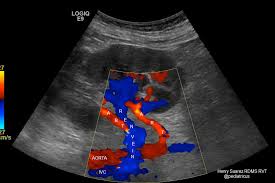

Doppler Ultrasound Of The Kidneys Ultrasound Vascular Ultrasound Ultrasound Sonography

It also allows to circumvent bowel gas and sometimes visualize the renal arteries better. The kidney wrongly senses the reduced flow as low blood pressure via the juxtaglomerular apparatus and releases a large amount of renin that converts angiotensinogen to angiotensin i. Kidney ultrasounds also called renal ultrasounds specifically target the kidneys and bladder.

The flank approach is practical for visualizing the mid and distal renal arteries more than the proximal renal artery. The central approach of renal transplant ultrasound is to evaluate for possibly treatable surgical or medical complications arising in the transplanted kidney. Any vessels identified must be traced to the kidney to confirm their identity. A renal artery doppler test is a type of ultrasound that measures the speed of blood flow in the arteries leading to the kidney explains webmd.